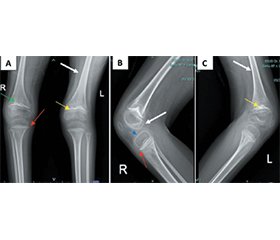

Цинга — клінічний прояв хронічного дефіциту вітаміну C — зазвичай вважається історичним захворюванням. Вітамін С (аскорбінова кислота) необхідний для синтезу колагену, біосинтезу карнітину та метаболізму нейромедіаторів. Труднощі з годуванням, вибірковість у харчуванні й залежність від опікунів у дітей із церебральним паралічем призводять до дефіциту вітаміну С, що обумовлює «прихований голод», який клінічно може нагадувати неврологічне регресування. Наведено випадок спастичної диплегічної форми дитячого церебрального паралічу (GMFCS IV) у п’ятирічної дівчинки, яка звернулася зі скаргами на рецидивуючий геморагічний гінгівіт та прогресуючу втрату здатності ходити. Протягом двох років її стан погіршувався — від ходьби з підтримкою до прикутості до ліжка з псевдопаралічем через виражений кістково-м’язовий біль. Під час фізикального огляду виявлено гіпертрофію ясен і тяжке недоїдання. Лабораторне обстеження показало критично низький рівень вітаміну С у сироватці крові (0,1 мг/дл). Рентгенограми колінних суглобів продемонстрували класичні ознаки цинги, включно з білою лінією Френкеля i шпорами Пелкана. Дефіцит вітаміну С призводить до порушення утворення колагену, крихкості кісток та капілярної нестабільності. Крім того, знижена активність дофамін-β-гідроксилази може викликати погіршення когнітивних і комунікативних функцій. Затримка діагностики в цьому випадку була зумовлена оромоторною дисфункцією, соціально-економічними чинниками та низькою клінічною настороженістю щодо дефіциту мікронутрієнтів у дітей із встановленими неврологічними розладами. Шестимісячне мультидисциплінарне втручання, яке включало призначення вітаміну C, цілеспрямовану нутритивну реабілітацію та інтенсивну фізіотерапію, сприяло значному функціональному відновленню. У пацієнтки відзначено суттєве поліпшення стану — вона знову змогла самостійно стояти та ходити з підтримкою. Цей випадок підкреслює важливість рутинного скринінгу мікронутрієнтів у дітей із неврологічними порушеннями для запобігання захворюваності та функціональному регресуванню, яких можна уникнути.

Scurvy, the clinical manifestation of chronic vitamin C deficiency, is commonly regarded as a historical disease. Vitamin C (ascorbic acid) is essential for collagen synthesis, carnitine biosynthesis, and neurotransmitter metabolism. Feeding difficulties, dietary selectivity, and caregiver dependence in children with cerebral palsy predispose them to vitamin C deficiency, resulting in “hidden hunger” that may clinically resemble neurological regression. We report a five-year-old girl with spastic diplegic cerebral palsy (GMFCS IV) who presented with recurrent hemorrhagic gingivitis and progressive loss of ambulation. Over two years, she deteriorated from assisted walking to bedbound pseudoparalysis due to severe musculoskeletal pain. Physical examination revealed gingival hypertrophy and severe malnutrition. Laboratory evaluation showed a critically low serum vitamin C level (0.1 mg/dL). Knee radiographs demonstrated classic scurvy features, including the white Frankel line and Pelkan spurs. Vitamin C deficiency leads to defective collagen formation, bone fragility, and capillary instability. In addition, reduced dopamine β-hydroxylase activity may contribute to cognitive and communicative decline. Diagnostic delay in this case was influenced by oromotor dysfunction, socioeconomic factors, and low clinical suspicion of micronutrient deficiency in children with established neurological disorders. A six-month multidisciplinary intervention, including vitamin C supplementation, targeted nutritional rehabilitation, and intensive physiotherapy, resulted in substantial functional recovery. The patient showed marked improvement, regaining independent standing and assisted walking. This case highlights the importance of routine micronutrient screening in neurologically impaired children to prevent avoidable morbidity and functional regression.